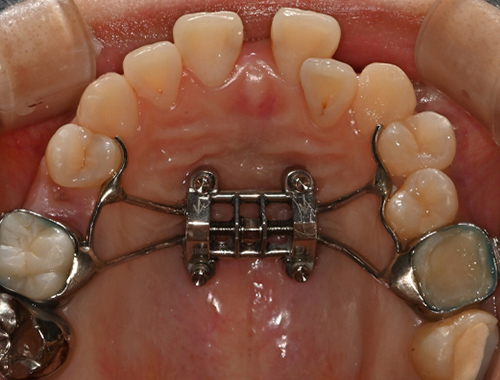

확장 전